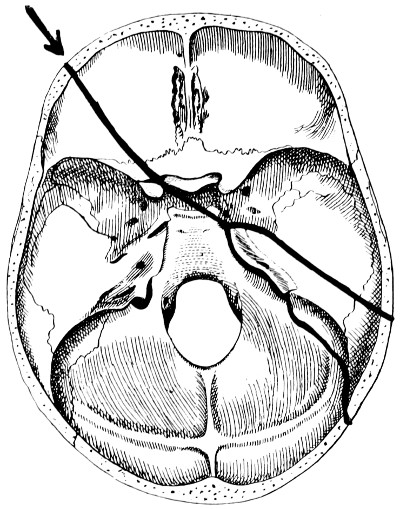

28. Illustrating the lines along which forces received on the vault are transmitted to the base 69

30. Plan of the base of the skull 77

31. To illustrate the relation of basic fractures to cranial nerves 81

32-37. The lines pursued by basic fractures 83-8